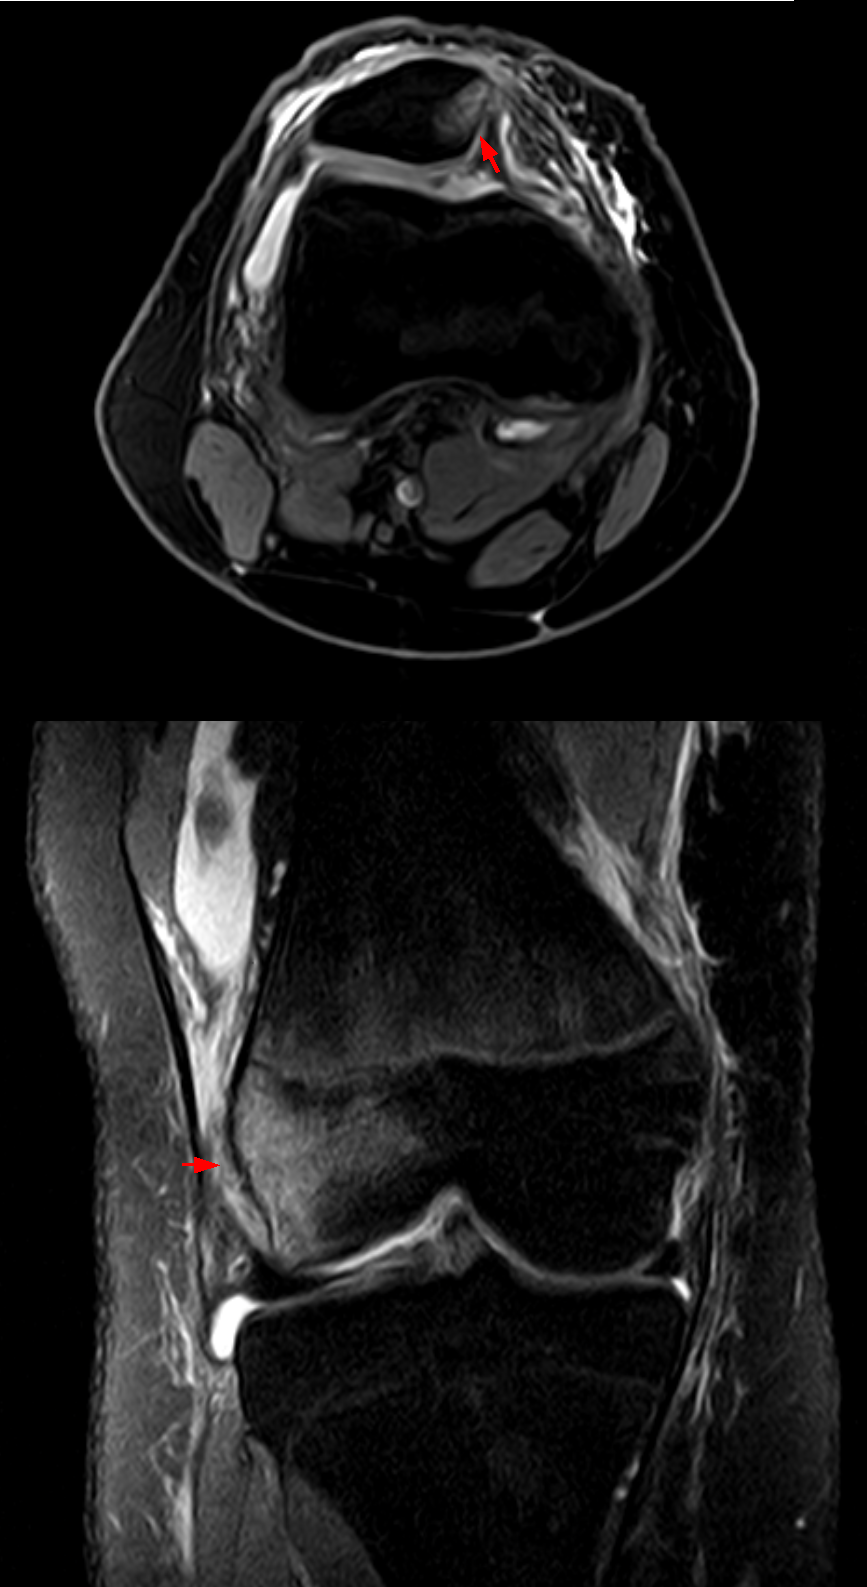

슬개골 탈구의 진단은 주로 무릎 촉진과 신체 검사를 통해 이루어지며[5], 그 심각성에 따라 4단계 등급으로 나뉜다.[5]

진단은 무릎을 직접 만져보아(촉진) 슬개골이 정상보다 더 많이 관절 안쪽으로 움직이는지 확인하는 방식으로 이루어진다. 간혹 보호자가 '무릎이 헐겁다'는 진단을 듣는 경우가 있지만, 이는 의학 용어가 아니므로 슬개골 탈구와 동일시해서는 안 된다.[5]

무릎이 헐거운 경우 슬개골 탈구가 나타날 수 있지만, 그렇다고 해서 반드시 슬개골이 탈구되는 것은 아니다. 슬개골 탈구가 있더라도 뒷다리를 간헐적으로 저는 증상 외에는 특별한 증상이 없거나 가벼울 수 있다. 신체 검사와 수동 조작이 진단에 가장 선호되는 방법이다. 상태가 심각해지면 심한 절뚝거림을 유발할 수 있으며, 이차적으로 골관절염이 발생하는 경우도 흔하다.[5]

슬개골 탈구는 심각도에 따라 4가지 진단 등급으로 나뉜다.[5]